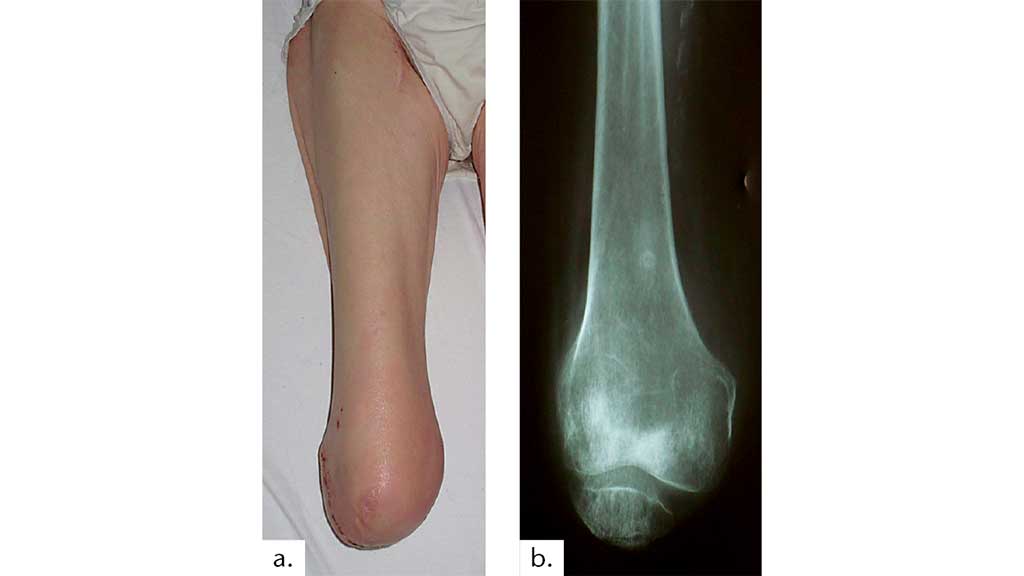

Fallvorstellung 3: ♀, 36,6 Jahre – Suizidversuch – lange Intensiv-

behandlung – Erhalt des Beines nach mehrfachen plastischen Operationen nicht möglich – Knieexartikulation – 14 Tage nach der Knieexartikulation voll endbelastbarer Knieexartikulationsstumpf (Abb. 15).